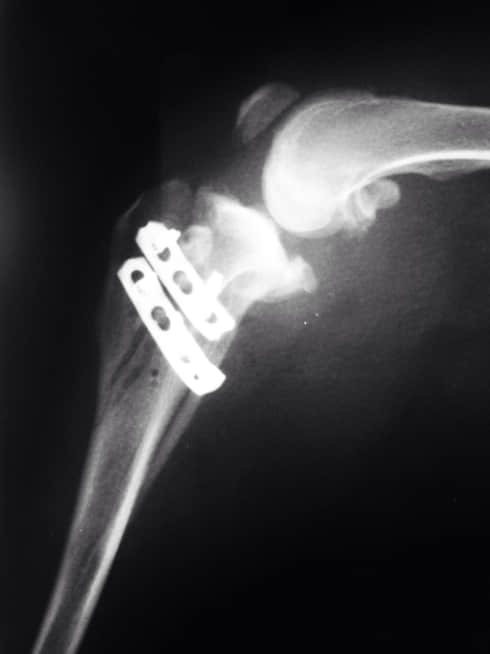

我问诊,是否以膝关节内侧肿胀为主?是否外侧无肿胀,抽屉运动是否异常?回答均乎。于是拟诊断为前十字韧带断裂或部分断裂,内侧半月板损伤。由于考虑到年龄和体重,建议施胫骨粗隆前移手术,以稳定膝关节,减缓半月板压力。同时进行生物陶瓷填充物植入。

术前,我们的冼医生为之进行了简单的理学检查。我们重新拍摄了膝关节x光,计算了手术的植入物宽度。准备好之后,我们开始对动物麻醉,上了监护。在消毒好,我们手术开始了十分钟之前,任麻醉师的冼医生示意让我停止手术。我不解,但必须听指挥。要知道,手术中最高权力者非主刀医师,而是麻醉师。

我加快了手术速度追赶时间,手术时间约做了一个半小时。期间只是调整了麻醉浓度和输液速度,并未补充传导阻滞的药品,手术出奇的顺利。